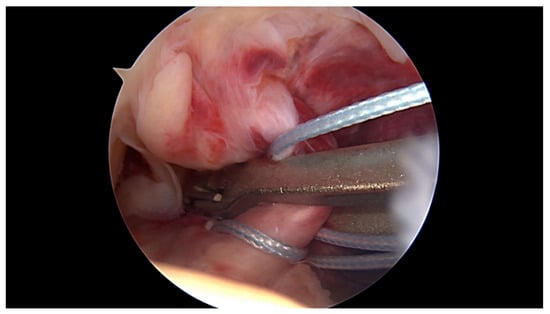

All surgeries were performed under spinal anaesthesia with the affected leg placed in an adjustable leg holder and with administration of an intravenous antibiotic prophylaxis. An examination under anaesthesia of the knee was performed prior to surgery in order to confirm ACL instability. The standard anterolateral and anteromedial portals were established to perform the arthroscopy to confirm all suspected findings with a probe. The ACL was assessed regarding tear pattern and tissue quality. When a proximal tear pattern with good tissue quality was identified (Figure 2), the patient was deemed eligible for arthroscopic ACL repair using SA: a labral scorpion suture passer (Arthrex, Naples, FL, USA) was used to pass a No. 2 FiberWire® (Arthrex, Naples, FL, USA) 3 times approximately 1 cm distal to the tear through the ACL remnant (Figure 3 and Figure 4). The femoral tunnel was drilled in anatomic manner within the footprint with 130 degrees knee flexion using a spade tip drill pin (Arthrex, Naples, FL, USA). An arthroscopic 45 degrees awl was used to perform a microfracture near the femoral footprint to enhance healing (Figure 5). Afterwards, a shuttling loop was passed through the femoral tunnel. The tibial drilling guide (Smith and Nephew, Andover, MA, USA) was placed at the anterior centre of the tibial footprint and a small skin incision at the anteromedial aspect of the proximal tibia was established to allow drilling and shuttling of a loop through the tibial tunnel. The tibial and femoral shuttling loop as well as the FiberWire® suture were retrieved through the anteromedial portal, the latter two placed in the tibial shuttling loop and passed through the tibial tunnel. Using the femoral shuttling loop, the SA construct containing a FiberTape® (Arthrex, Naples, FL, USA) armed TightRope® (Arthrex, Naples, FL, USA) and the FiberWire® were carefully shuttled through tibia and femur so that the TightRope® button flipped at the femoral cortex. The FiberTape® was fixed distally at the anteromedial tibia with a 4.75 SwiveLock® (Arthrex, Naples, FL, USA) with the knee in full extension. Subsequently, the FiberWire® suture and TightRope® tensioning suture were knotted on tension completing the ACL repair (Figure 6). Concomitant meniscal injuries were addressed either with direct repair (RapidLoc®, Mitek Products, Westwood, MA, USA) or with cautious partial resection when repair was deemed not feasible due to the configuration of the tear or pre-existing degenerative meniscopathy (Table 1). Concomitant chondral injuries were carefully smoothed or prudently underwent nano-fracture under direct vision.

Figure 3. The labral scorpion suture passer is placed approximately 1 cm distal to the ACL tear.